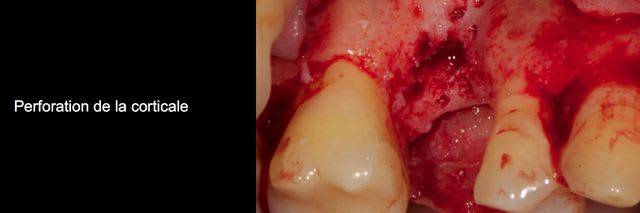

Bon j'ai extrait la dent et maintenant y a un gros trou.

Bon ben voilà j'ai réalisé une ROG avec une membrane PTFE armé titane.

bien sûr les photos sont dans le désordre encore une fois ;)